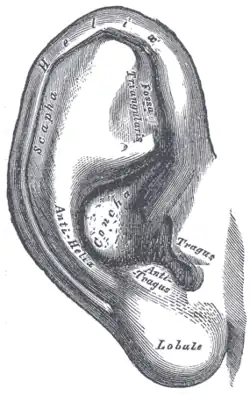

Die Gow-Gates-Technik (benannt nach dem Erstbeschreiber, dem Australier George Gow-Gates) wurde 1973 entwickelt, um die Misserfolgsquote der Leitungsanästhesien auf nur 5 % zu vermindern. Mittels einer einzigen Injektion werden mehrere Leitungsanästhesien, nämlich des Nervus alveolaris inferior, des Nervus lingualis, des Nervus mylohyoideus, des Nervus auriculotemporalis und – mit 75-prozentiger Wirkung – auch des Nervus buccalis, durchgeführt. Hierzu wird ein Depot des Lokalanästhetikums am Kondylenhals des Unterkiefers gesetzt.[51] Bei weit geöffnetem Mund wird an der Incisura intertragica der Kondylenkopf ertastet und dient als „Zielmarke“. Die Injektionsnadel (Gaugegröße 27) wird zu zwei Dritteln in die Umschlagfalte hinter dem Tuber maxillae in den paratubären Raum eingeführt und der Knochenkontakt am Kondylenhals gesucht. Der Nervenstrang selbst liegt distal des Kondylus. Nach Aspirationstest und erfolgter Injektion soll der Patient den Mund eine weitere Minute weit geöffnet halten. Wegen der geringen vaskulären Versorgung dieses Bereichs und des dadurch verlangsamten Abtransports des Lokalanästhetikums wird ein Lokalanästhetikum (Mepivacain – Scandicain, Meaverin) ohne Vasokonstriktor verwendet. Die Injektion ist für den Patienten kaum wahrnehmbar.[52] Der Patient sollte zuvor aufgeklärt werden, dass bei der Gow-Gates-Lokalanästhesie eine Gesichtshälfte mehr oder minder vollständig anästhesiert sein wird.

Die Incisura intertragica liegt zwischen Tragus und Antitragus

Die Incisura intertragica liegt zwischen Tragus und Antitragus -